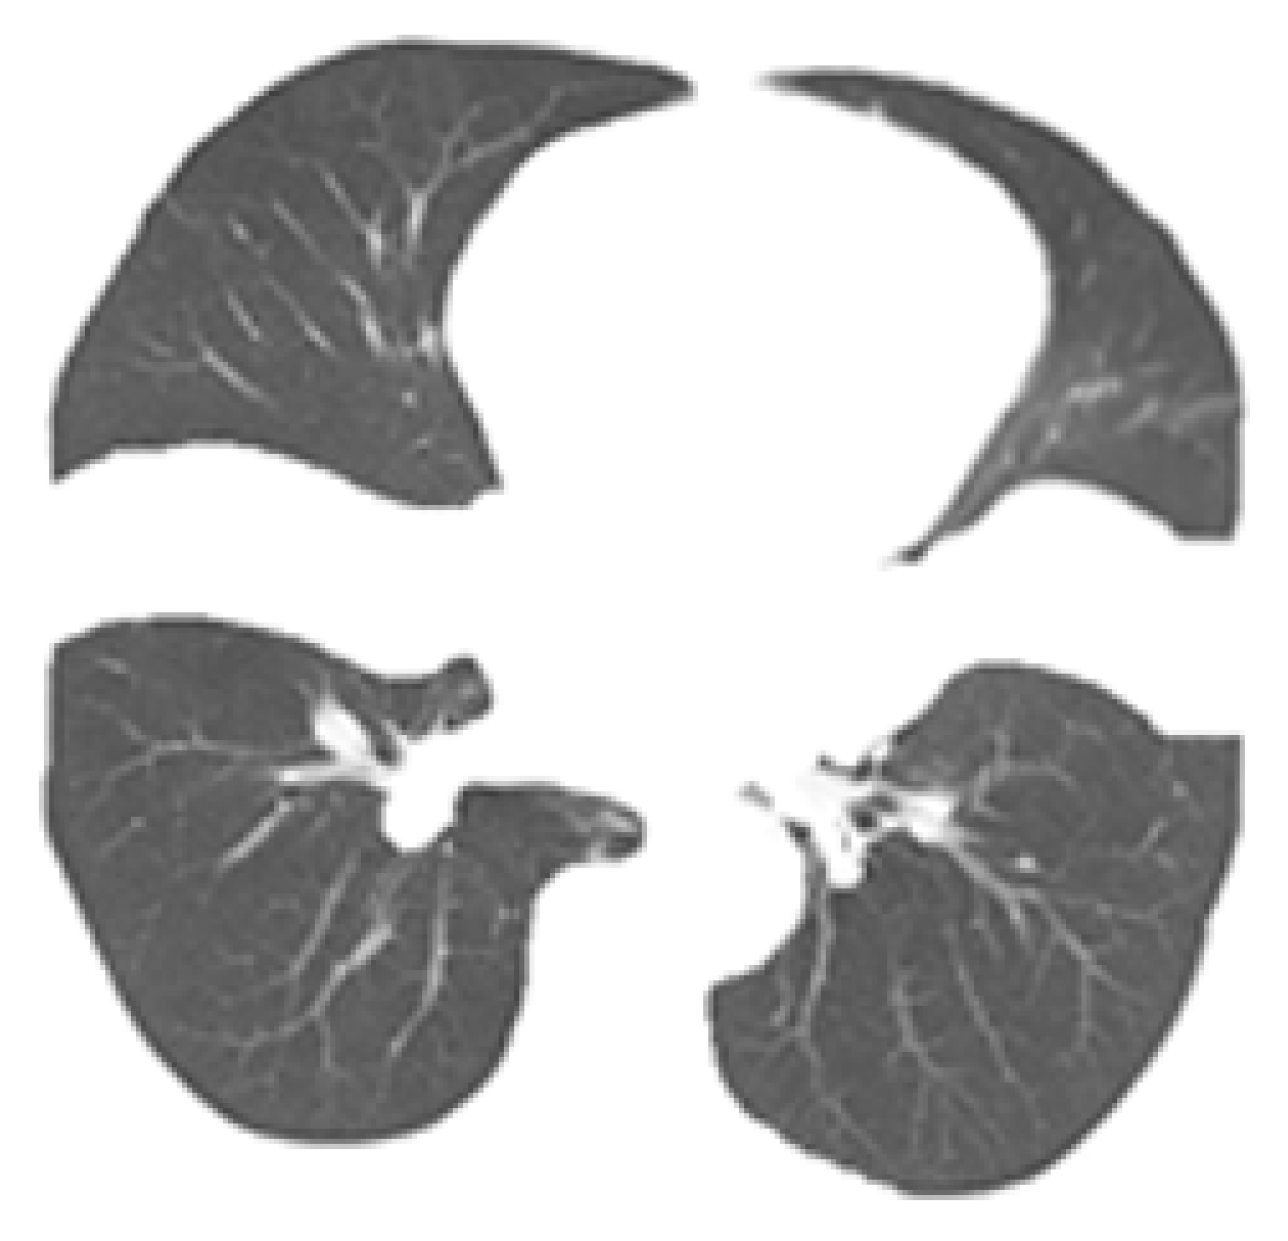

The structure of the RDU-Net model designed above is shown in Figure 3. This design can avoid the information loss caused by downsampling, expand the receptive field better, and effectively reduce the holes generated in the segmentation process. Table 4 shows the comparison of advantages and disadvantages between U-NET and RDU-NET in segmentation. Figure 4 shows the comparison between the original image and the actual effect of lung segmentation using U-Net and RDU-Net. Figure 5 is the image of each lung lobe after using RDU-Net for lung lobe segmentation.

Figure 4. Comparison of two methods of lung lobe segmentation. (a) Original image. (b) U-Net lung lobe segmentation. (c) RDU-Net lung lobe segmentation.

Bioengineering 09 00359 g004

Figure 5. Segmentation image of lung lobe. From left to right from top to bottom as follows: right-up lobe, left-up lobe, right-down lobe, and left-down lobe.